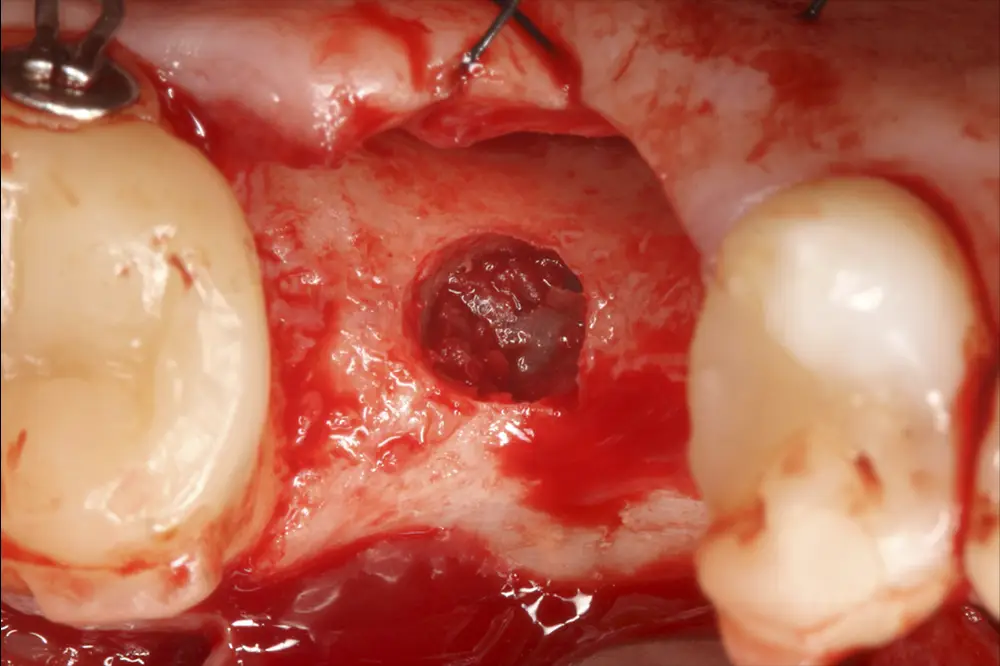

Figs. 10 y 11. Fresado de la zona, colocación del injerto y del implante.

En este caso, la paciente acude con la exodoncia realizada hace dos años de la pieza 16 y una gran atrofia vertical, existiendo únicamente 1 mm en algunas zonas de la cresta, como el área más vestibular, y hasta 3 en la zona más palatina (fig. 9). Procedemos a la realización del fresado tal como se ha descrito en el caso anterior y colocamos el mismo tipo de injerto (autólogo y PRGF- Endoret) y un implante de 4,5 mm de longitud (fig. 10 y 11). Tras la cicatrización a los 4 meses, observamos el aspecto de la zona de la colocación del implante, donde tenemos ahora una altura de 7 mm (fig. 12).